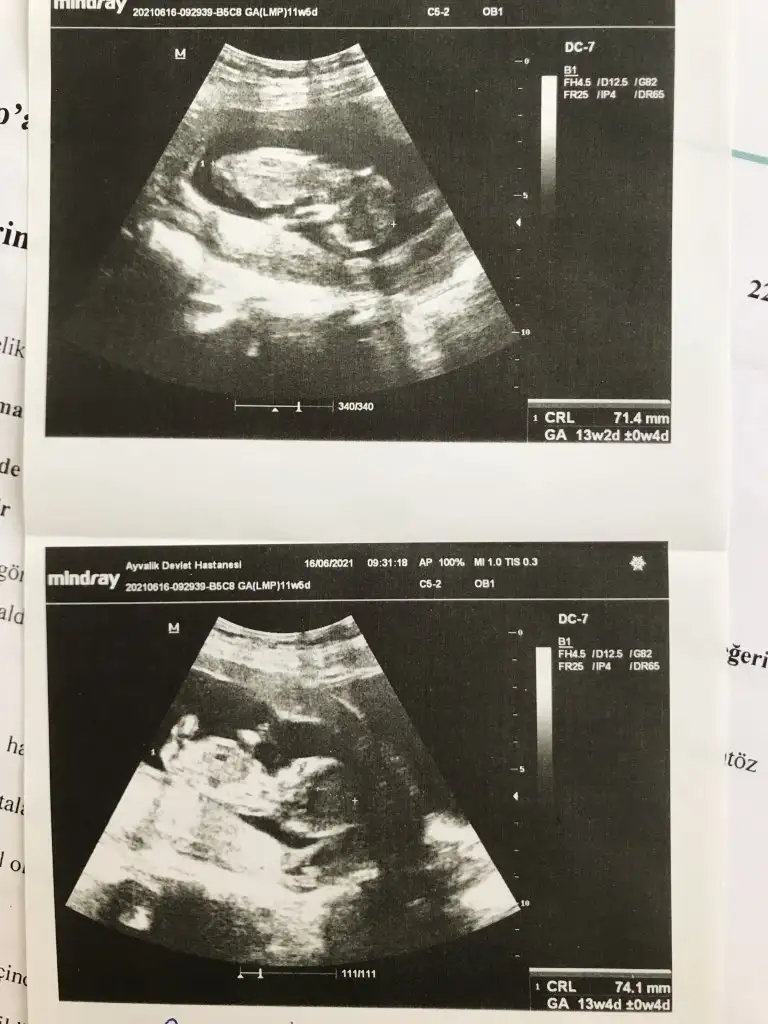

Benim ikiz bebeklerime de bir tahminde bulunurmusunuz

Eki Görüntüle 2889233

Eki Görüntüle 2889229 Eki Görüntüle 2889231

Haftası büyük olan erkek

haftasi küçük olan kız![]()